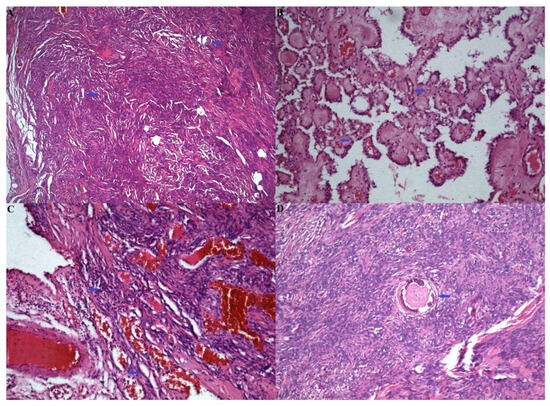

2.2. Pathological Examination